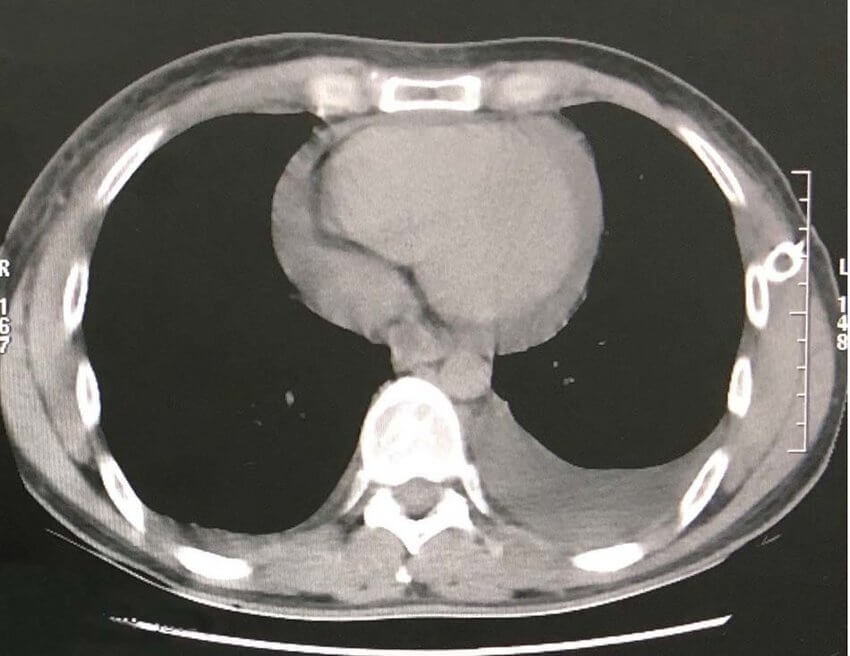

CT shows large 10cm anterior mediastinal mass. Patient’s O2 saturation falls to 89%. Your consultant asks you to manage.

Confirmed exudative Chylothorax due to likely malignancy. CECT shows large 10cm anterior mediastinal mass.